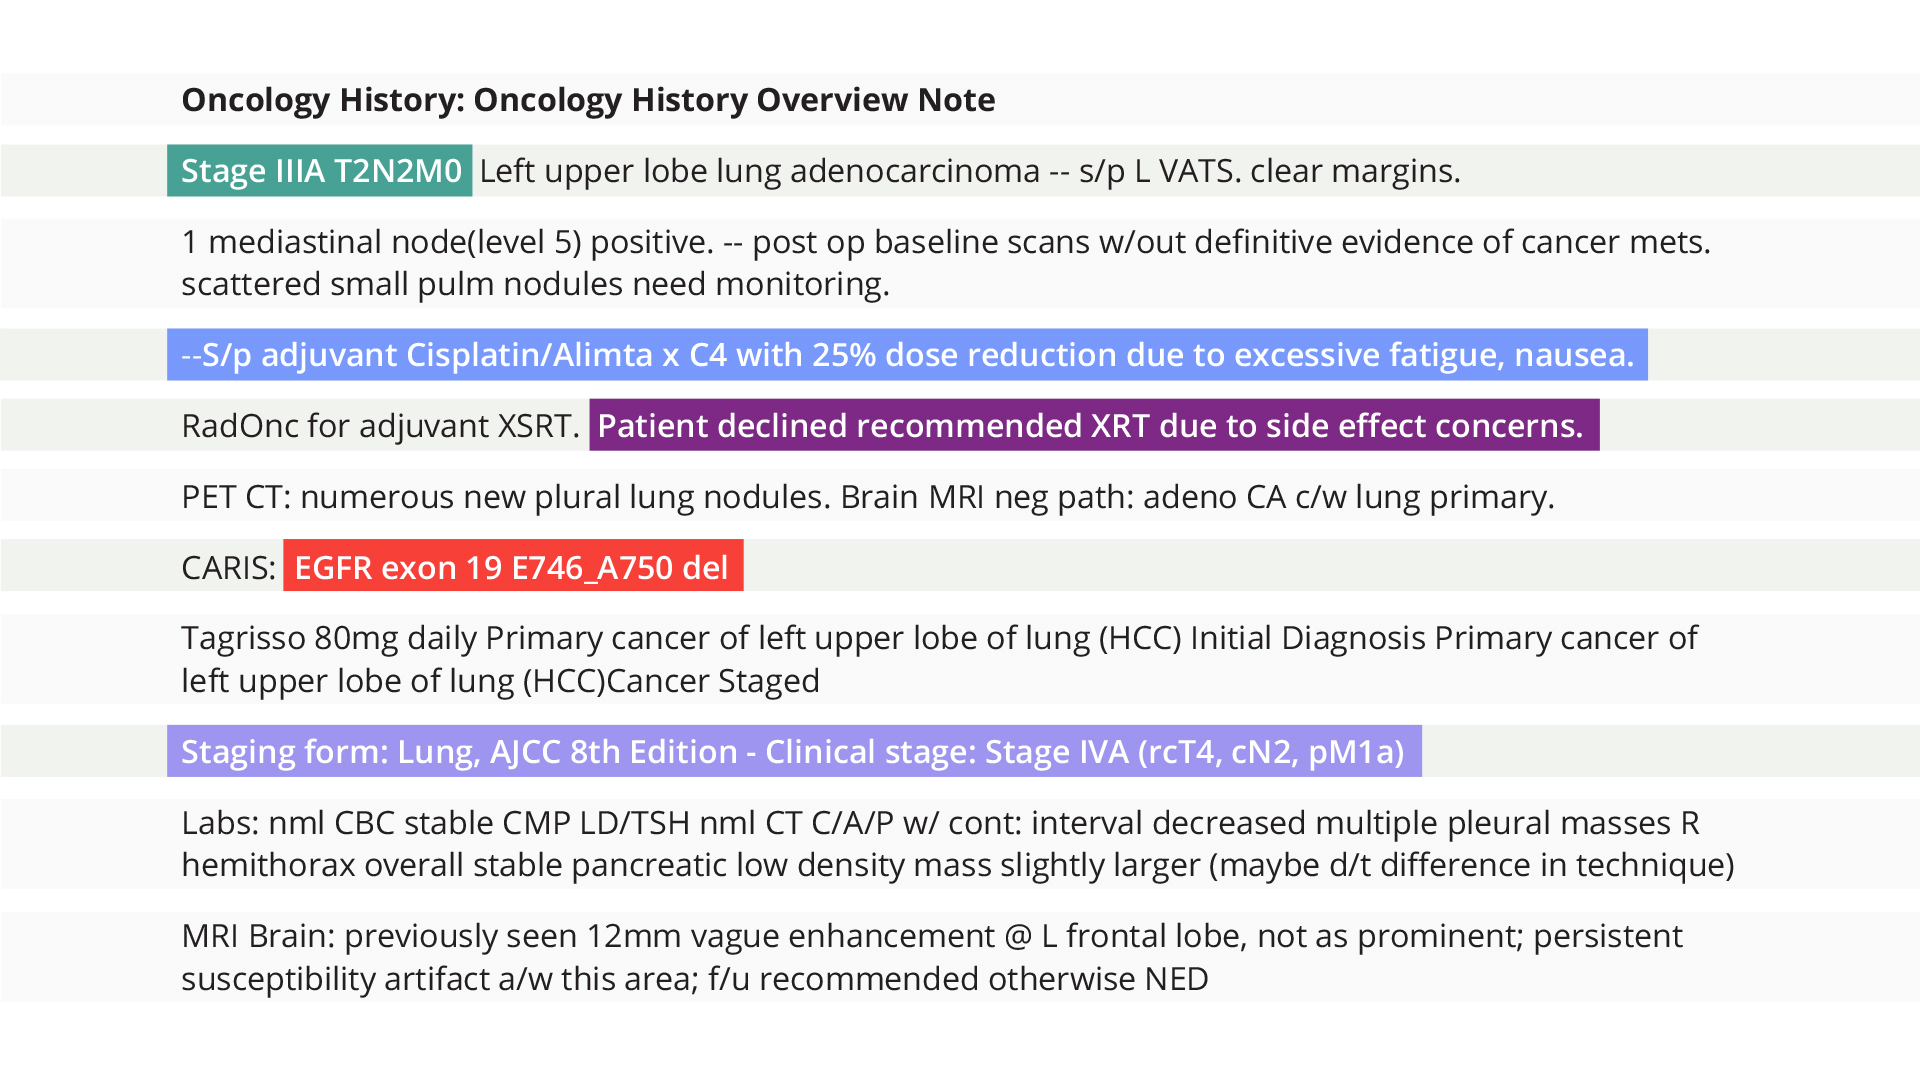

More than 7 billion clinical notes

The Truveta Language Model cleans and structures data from notes at scale, enabling researchers to understand patients’ complete clinical context and answer novel research questions.